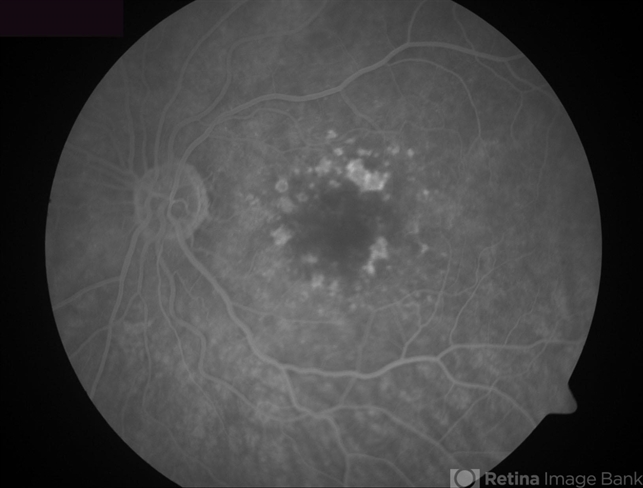

- Dry Age-Related Macular Degeneration - Calcified drusen

- calcified drusen, dry age-related macular degeneration (dry AMD), age-related macular degeneration (AMD)

- Fluorescein angiogram of a 72 year-old patient with dry age-related macular degeneration and calcified drusen.